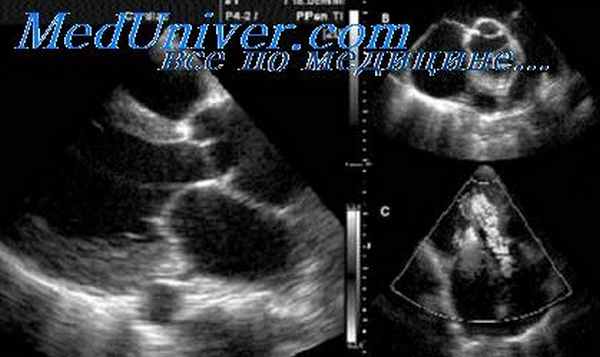

У значительной части больных с хронической алкогольной интоксикацией (по нашим данным, у 15%) развитие алкогольной кардиомиопатии сопровождается выраженными нейроциркуляторными расстройствами по типу вегетативно-сосудистых пароксизмов. Определенное значение в этиологии нейроциркуляторной дистонии имеет влияние алкоголя на функции высшей нервной деятельности и вегетативных центров (Г. Ф. Ланг, 1957; В. Ф. Зеленин, 1956). По мнению P. D. White (1946), наиболее частыми кардиоваскулярными реакциями на алкогольную интоксикацию являются нейроциркуляторная дистония или пароксизмальная тахикардия.

Клиника этого варианта поражения сердечно-сосудистой системы при алкоголизме имеет свои особенности. У человека, прежде безболезненно в течение ряда лет злоупотреблявшего спиртными напитками, внезапно, обычно на второй день после приема особенно большой дозы алкоголя, развивается приступ разлитой боли в левой половине грудной клетки, сопровождающийся глубоким учащенным дыханием, сильным сердцебиением, выраженным общим тремором и резким беспокойством. Часто к указанным симптомам присоединяются головокружение, тошнота, усиленное потоотделение.

Нередко на первый план выступает инспираторная одышка, которую можно уменьшить, отвлекая внимание больного. Сердцебиение в большинстве случаев связано с ощущением сильных ударов собственного сердца без выраженной тахикардии, причем сердечный толчок действительно усилен и виден при осмотре. По окончании приступа выделяется в большом количестве светлая прозрачная моча. Приступ продолжается от 30—40 мин до нескольких часов и очень напоминает «большой кортико-вегета-тивный синдром» (В. Ф. Зеленин, 1956) или гипоталами-ческий криз, который, по мнению И. Г. Уракова (1973), является своеобразным проявлением алкогольной энцефалопатии.

Пульс во время приступа немного учащается, в отдельных случаях появляются экстрасистолы, реже — пароксизмальная тахикардия. Тоны сердца становятся громче обычного, артериальное давление несколько повышается, главным образом за счет систолического. После нейроциркуляторного криза иногда обнаруживается нейтрофильный лейкоцитоз.

Вне приступа при объективном обследовании больных выявляются те же отклонения, что и у остальных больных с латентной алкогольной кардиомиопатией: небольшое смещение левой границы относительной тупости сердца влево, ослабление 1-го тона на верхушке, иногда небольшая тахикардия, умеренное увеличение печени. Неврологический статус характеризуется высокими сухожильными рефлексами, разлитым стойким дермографизмом, тремором век и пальцев вытянутых рук, а также гиперальгезией кожи левой половины грудной клетки.

Бурные вегетативные кризы с явлениями гиперкинетической циркуляции (очень демонстративной на баллистокардиограмме) могут быть связаны с усиленной выработкой адреналина, но более вероятна их связь с гиперкинетическим синдромом, обусловленным, по-видимому, гиперактивностью бета-адренергических рецепторов (R. Gorlin и соавт., 1959; Е. Frohlich, H. Dustan и J. Page, 1966); во всяком случае их течение значительно смягчается бета-блокаторами (А. М. Скупник, 1971). Больные очень тяжело переносят эти пароксизмы ввиду сопровождающего их кардиофобического симптомокомплекса и на некоторое время прекращают употребление алкоголя.

Таким образом, ранняя стадия алкогольной кардиомиопатии обычно протекает в известной мере латентно, сопровождаясь у отдельных больных описанными выше циркуляторными пароксизмами. К врачу больной обращается лишь тогда, когда его начинает беспокоить сердцебиение. Тахикардия, нередко сочетающаяся с экстрасистолией, а также пароксизмы мерцательной аритмии, наступающие в относительно молодом возрасте, являются первыми клиническими признаками алкогольной кардиомиопатии. Эти симптомы, обнаруженные при отсутствии признаков какого-либо органического заболевания сердца или гипертонической болезни, должны побудить врача собрать самый тщательный анамнез, выяснив, не злоупотребляет ли больной алкоголем.